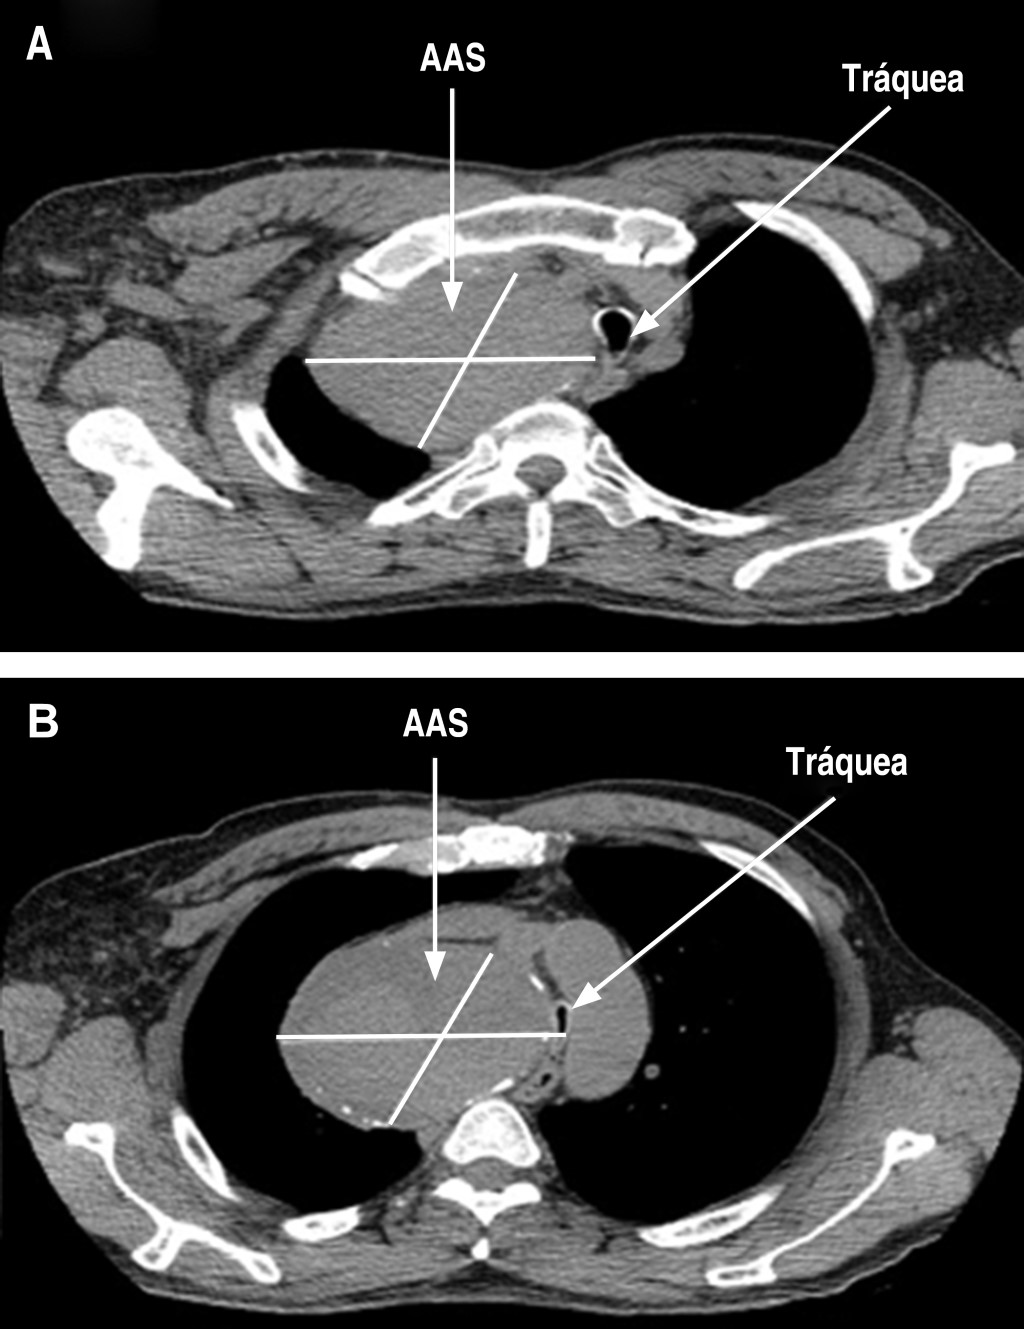

Sedoanalgesia with ketodex for selective intubation in the resection of a giant aneurysm of the subclavian artery associated. Case report

A giant subclavian artery aneurysm associated with superior vena cava syndrome occurs infrequently. Complexity of the approach will depend on the size, shape, and position of the aneurysm, particularly when a potential collapse of the airway is expected due to the compressive effect of the mediastinal mass after using neuromuscular relaxant for airway approach. We present a case in a 57-year-old male with shortness of breath in dorsal that increases with left lateral decubitus during five years of evolution. Radiological studies reported giant mediastinal mass compatible with an aneurysm of the right subclavian artery, which produces critical compression and airway displacement, particularly in trachea at level of the carina. The patient is scheduled for resection of the aneurysm and requires selective intubation for isolation of the right lung during surgery which was performed with the awake patient technique using sedoanalgesia with ketodex. The objective of the case is to share the experience using ketodex as an alternative for the tolerance of procedures that requires the cooperation of the patient where propofol and neuromuscular relaxant may be a problem for airway permeability and approach.

Figure 2